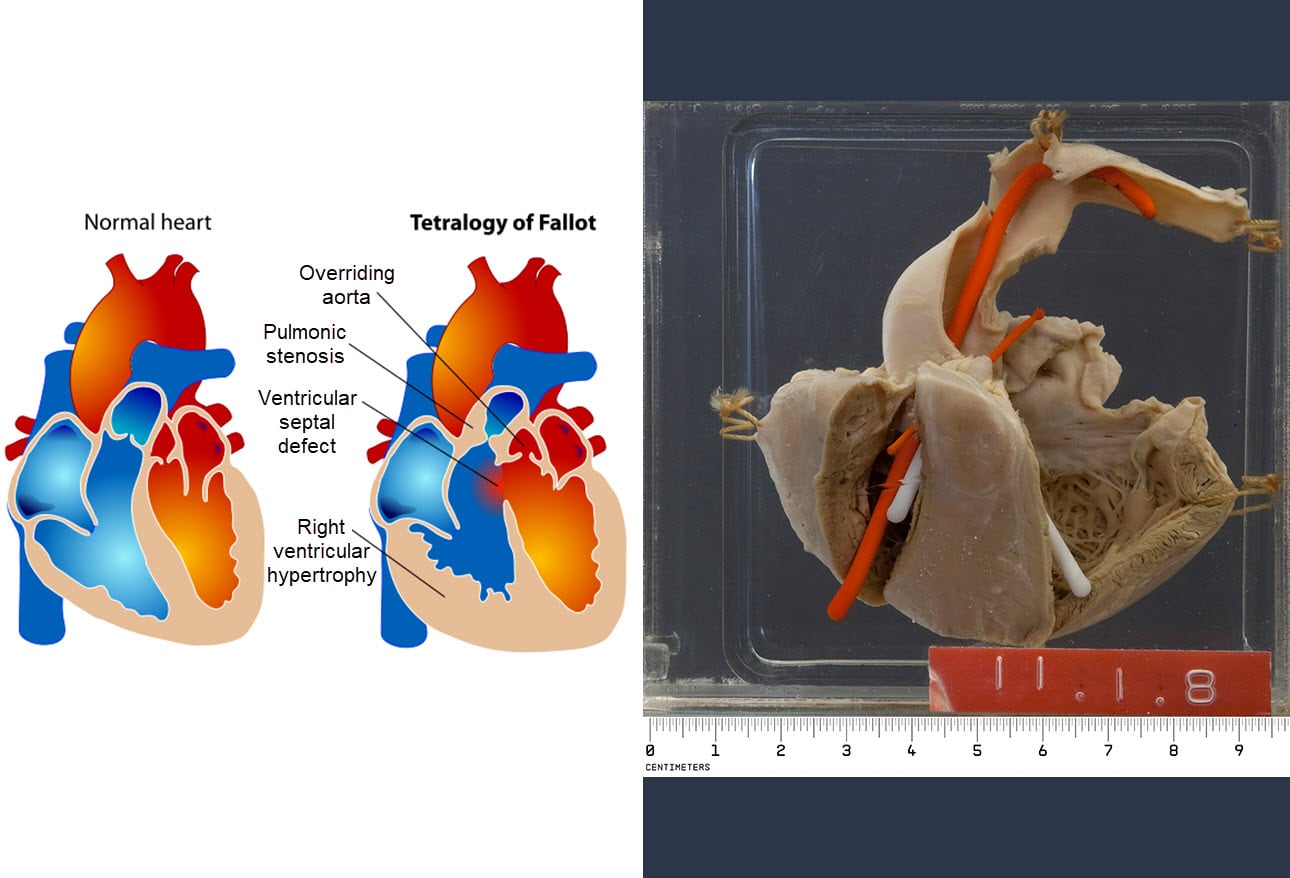

Sudden Cardiac Death

www.rsimmanuel.comSudden cardiac death

Sudden Cardiac Death

www.rsimmanuel.comSudden cardiac death